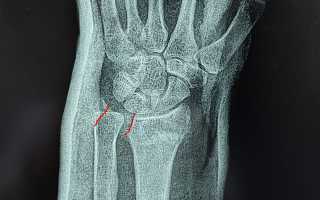

Диагноз устанавливается на основе сбора анамнеза, проведения объективного осмотра пациента и выполнения рентгенологического исследования.

Специалисты рекомендуют проводить диагностику с использованием рентгенографии для подтверждения диагноза и определения степени повреждения. В большинстве случаев лечение включает иммобилизацию конечности и физиотерапию, что способствует восстановлению функции руки. Важно также учитывать индивидуальные особенности пациента, такие как возраст и уровень физической активности, что может повлиять на выбор метода лечения. Эксперты подчеркивают, что ранняя реабилитация и соблюдение рекомендаций врача играют ключевую роль в успешном восстановлении.

Диагностика обычно включает физический осмотр, а также рентгенографию для подтверждения наличия перелома. В некоторых случаях может потребоваться МРТ или КТ для более детального изучения повреждений.